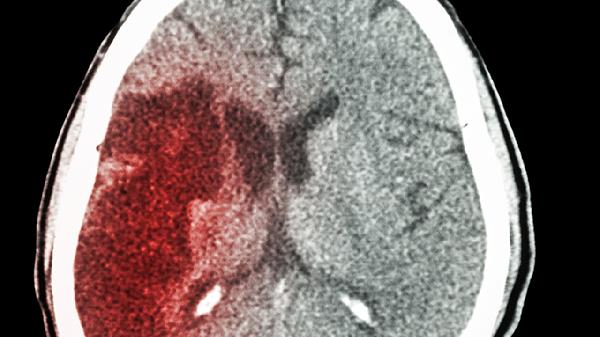

耳朵频繁出现6个信号,提示脑血管已“不堪重负”,警惕脑梗?

耳朵里藏着脑血管的"求.救信号"?这些异常声响千万别当耳鸣处理!最近发现不少年轻人开始抱怨耳朵里总有奇怪的动静,以为是工作压力大导致的耳鸣。但你可能不知道,某些特殊的耳部症状,可能是脑血管发出的"红色警.报"。